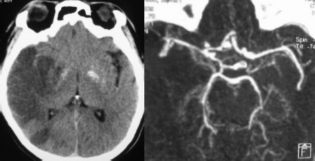

Hình 3.2a. Minh họa tắc động mạch cảnh trong hai bên – ca đầu tiên. Bệnh nhân TAK, nam, 49 tuổi, nhồi máu não phần trước (nhánh nông trên) động mạch não trước phải, với nhồi máu cũ ranh giới sau trái, tắc động mạch cảnh trong hai bên, với bàng hệ thấy được là hai nhánh nhỏ từ động mạch cảnh ngoài mỗi bên nối vào đoạn xương đá của động mạch cảnh trong (mũi tên). Động mạch não giữa phải (cùng bên) hẹp nặng đầu đoạn M2